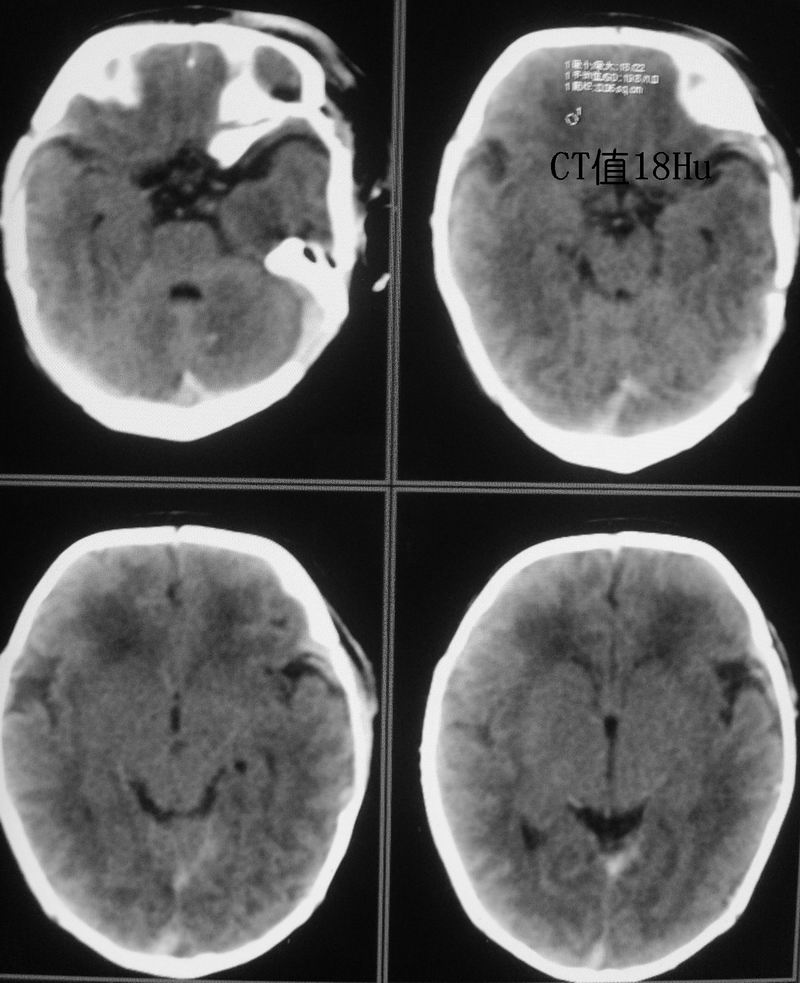

新生儿,男性,5天,出生时有短暂窒息史。现一般情况较好,面色红润,无明显发绀,原始反射尚可。经治医生和家属均不放心,要求ct。

小孩脑实质内可见多发对称性低密度灶,ct值17~20hu,我也考虑有缺血缺氧性脑病存在。

可问题是患儿虽有短暂的窒息史,却并没有明显的临床症状,实在不好解释。这就牵涉到新生儿的脑的正常ct值的问题,为此专门查了一点资料:

曹连义等曾报道足月新生儿脑组织ct值明显低于儿童及成人,建议新生儿期ct正常值为18~40 hu,低于18 hu为低密度[1-2]。对不同胎龄新生儿脑组织ct值正常范围及平均值国内未见报道。本研究显示即使新生儿期若胎龄不同,各部位脑组织(小脑、脑干、基底节、丘脑、白质、灰质)ct值均明显不同,胎龄越小,脑ct值越低,与国外学者报道一致[3]。其原因:(1)与脑组织含水量有关,胎龄越小,脑组织含水量越多;(2)胎龄越小,神经细胞髓鞘形成越不完全。故足月新生儿脑组织ct值正常范围不适用于早产儿,不同胎龄新生儿应有不同的正常值,这样才不致于将早产儿正常发育过程中的脑组织低密度误诊为脑水肿、缺氧缺血性脑病。

新生儿缺血缺氧性脑病的诊断应紧密结合临床.片上所见之对称性稍低密度影,很可能是窗宽窗位未调好,本人在工作中也遇到过这种情况,调节好窗宽窗位可避免误诊.新生儿及儿量脑细胞水份含量多于成人,因此脑实质密度更低,脑沟亦较浅.

新生儿缺血缺氧性脑病的诊断应紧密结合临床;脑白质ct低于18hu考虑缺血缺氧改变。